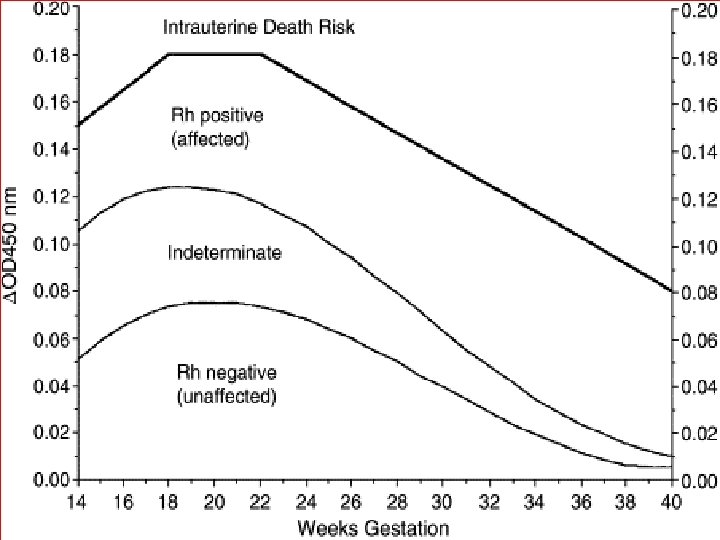

Liley chart Originated by liley in 1961, he compared ∆OD 450 measurements with fetal outcome in 101 isoimmunized pregnancies and showed that Mild, Moderate, or Sever fetal anemia could be predicted according to which of three zones the bilirubin level was plotted into ∆OD 450 = optical density deviation.

Queenan curve (Deviation in amniotic fluid optical density at a wavelength of 450 nm in Rh-immunized pregnancies from 14 to 40 weeks' gestation)

Zone 1 →fetus unaffected (Rh negative) or have only mild disease →repeat sampling in 2 to 3 weeks Zone 2→ if in lower part→ fetus at moderate risk→ HB level between 11 to 13 g/dl whereas in the upper part HB level between 8 to 10. 9 g/dl → repeat sampling within 1 to 2 weeks if in lower part, if in upper part delivery is indicated.

Zone 3→ severely affected fetus with HB level of less than 8 g/dl and without therapy death is predicted within 7 to 10 days immediate fetal red blood cell transfusion or delivery ACCORDING TO GESTATIONAL AGE l